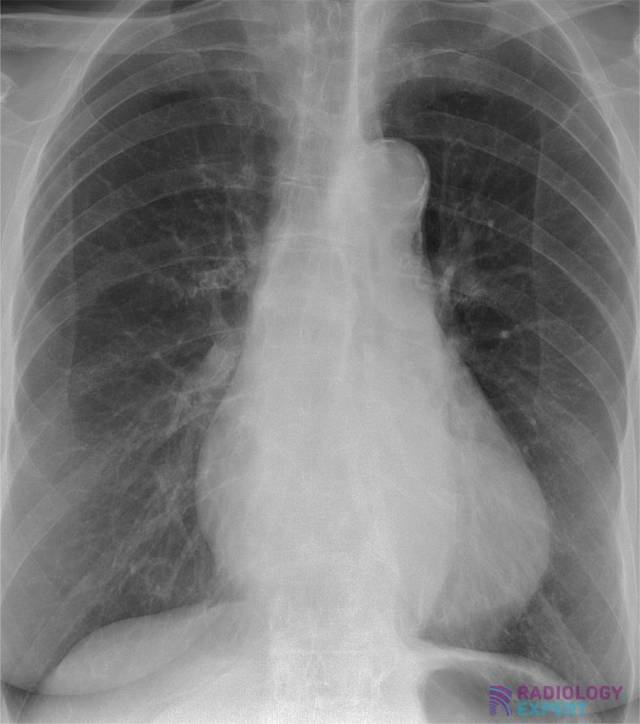

Chest X Ray To Diagnose Heart Failure . The following signs indicate heart failure: They could be taken in the health care professional’s office or in a separate radiology lab. Tests that may be done to diagnose heart failure may include: Alveolar edema with perihilar consolidations and air bronchograms (yellow arrows); A displaced cardiac apex, a third heart sound, and chest radiography findings of venous congestion or interstitial edema are useful in identifying heart failure. Blood tests can help diagnose diseases that can affect the. Changes in the size and shape of your heart may indicate heart failure, fluid around the heart or heart valve problems. Because the outlines of the large vessels near your.

Changes in the size and shape of your heart may indicate heart failure, fluid around the heart or heart valve problems. The following signs indicate heart failure: Because the outlines of the large vessels near your. Tests that may be done to diagnose heart failure may include: Alveolar edema with perihilar consolidations and air bronchograms (yellow arrows); A displaced cardiac apex, a third heart sound, and chest radiography findings of venous congestion or interstitial edema are useful in identifying heart failure. Blood tests can help diagnose diseases that can affect the. They could be taken in the health care professional’s office or in a separate radiology lab.

Heart Failure Chest X Ray